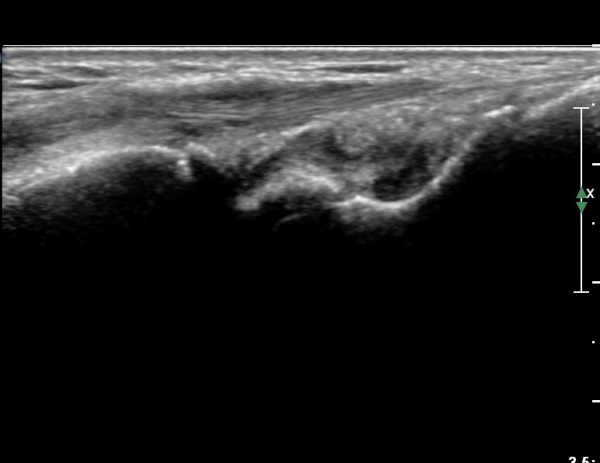

¼Õ¸ñÀÇ Á¾´Ü¸é°Ë»ç¿¡¼­ ¼Õ¸ñ °üÀý³» ºÎÁ¾ÀÌ °üÂûµÊ(»çÁø 1).

ÃÊÀ½ÆÄ°Ë»ç´Â ¹æ»ç¼±°Ë»ç¿¡¼­ º¸ÀÌÁö ¾Ê´Â ¼ÕÀ̳ª ¹ßÀÇ ¹Ì¼¼°ñÀý Áø´Ü¿¡ ¸Å¿ì À¯¿ëÇÏ´Ù.